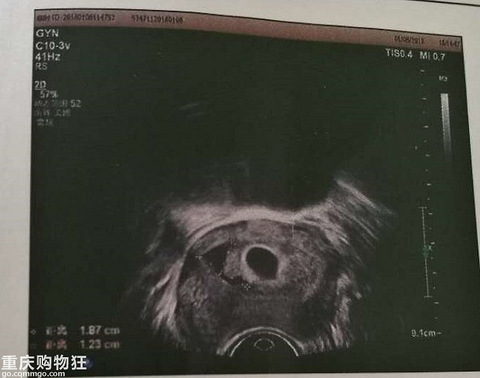

还记得那天晚上,老婆神秘兮兮的递给我一份检查单,大大咧咧的我靠在沙发上,接过单子像个小学生一样认真看起来。妇幼保健院几个赫然大字映入我眼帘,当时脑袋也是一片空白,只是习惯性继续往下,看见一幅图,图片里面有个小黑洞,这是我直观看到的,(难道是让我看图写话吗)然后一排小字:子宫后位,形态饱满,肌层回声欠均质……再往下:宫内早孕云云。 我去,我心想,早孕,不能啊,这些个年(耍朋友到那一刻,我们等了14年